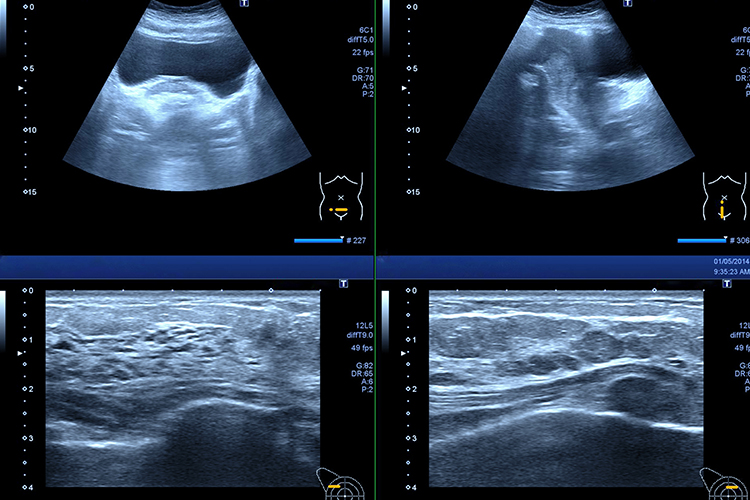

エコー検査

高周波音波を利用して体内組織を視覚化し、臓器の形や大きさ、動きなどを確認する検査です。犬や猫では、主に心臓、肺、肝臓、胆嚢、腎臓、膀胱、卵巣、子宮、前立腺、脾臓、十二指腸、副腎、腹腔リンパ節などの臓器を確認することができます。